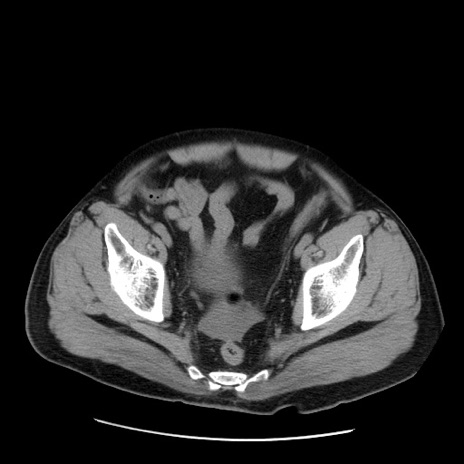

症例20(横断像)

【症例】 60歳代男性

【主訴】 腹部膨満、嘔吐

【現病歴】5日前頃より倦怠感を認め食事量減少し4日前の朝嘔吐、食事摂取困難となった。 3日前近医受診し点滴施行され整腸剤などを処方された。 当日他院を受診し、腹部膨満著明、炎症反応の上昇(CRP10.8、WBC11200)あり、紹介受診となる。

【身体所見】 意識JCS1 受け答えがはっきりしないBP 111/57mHg、 P 67bpm、、BT35.2°C、SpO2 97%(RA)、 腹部:膨隆、打診で鼓音あり、全体的に圧痛有り、腸蠕動音(-)、反跳痛ははっきりせず。

【データ】WBC 11400、CRP 14.20